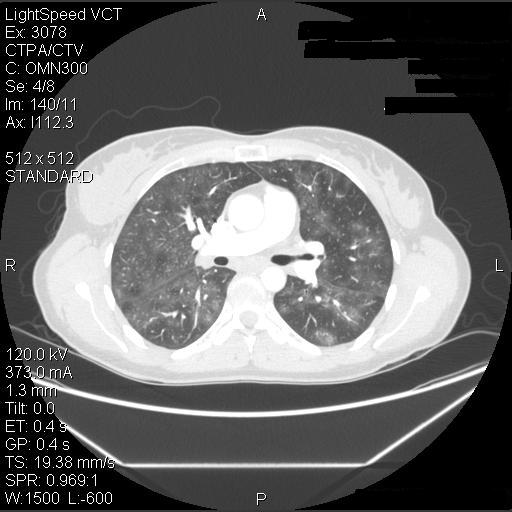

The patient was advised to avoid all possible agents in her environment which could have triggered hypersensitivity pneumonitis – the barn itself, horse-feed and horse-feed supplements, pigeons, and the hot tub. Since she did not have help on the farm she was not able to avoid the barn or feeding the horses but she did stop using the feed supplement and avoided the barn loft. Due to the severity of her symptoms, she was started on prednisone, initially 25 mg per day. She had a marked improvement in her symptoms, with a return to almost normal exercise tolerance and resolution of her pulmonary function abnormalities within a few days. She then returned to her usual activities without recurrence of symptoms although she continued to avoid the horse-feed supplement. Her pulmonary function testing progressively improved (Table 3), and CT scans 2 months and 6 months later also progressively cleared (Figure 5).